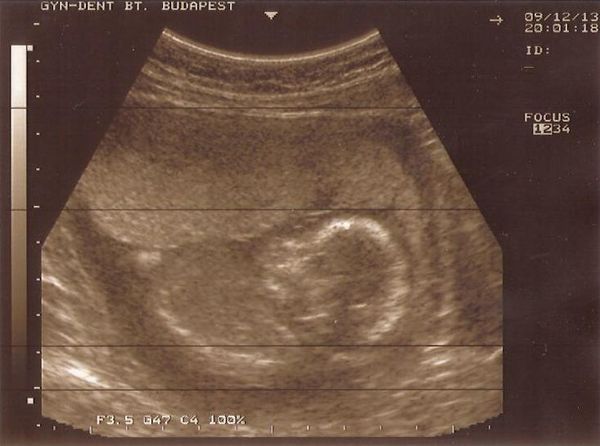

? Kb. 1 hete folyamatosan fáj a hasam, de hát múlt kedden voltunk UH-n, így azzal nyugtatom magam, hogy nagy baj nem lehet. Péntek este meg úgyis megyünk a genetikai UH-ra, addig meg csak kibírom, és remélem nem jön vissza az erősebb fájdalom. Ott meg megkérdezem majd a dokit, mit mond erre.